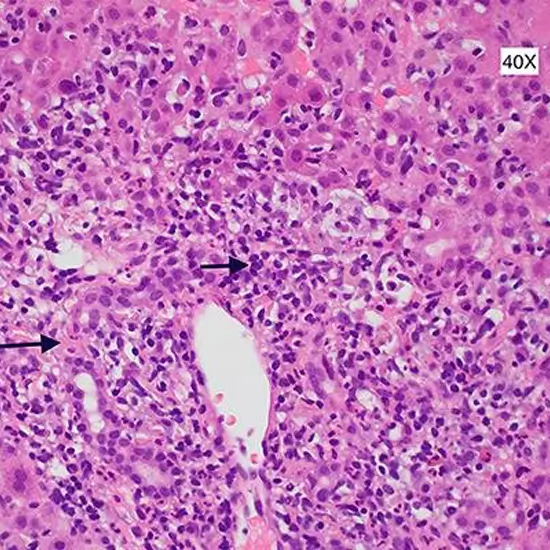

Histopathology liver biopsy is a procedure to draw out a small piece of liver tissue to examine under a microscope. This procedure is to diagnose liver disease or damage and its severity.

Doctors recommend this procedure when other test findings indicate liver issues but are unable to find them exactly. It is helpful in the diagnosis of the problems and the stages of the problems such as chronic hepatitis B or C, alcoholic liver, Wilson’s disease, and biliary cirrhosis, etc. It also helps doctors in the treatment plan and monitors the effects of ongoing treatment. This test is taken as post liver transplant procedure to monitor the condition of the liver.